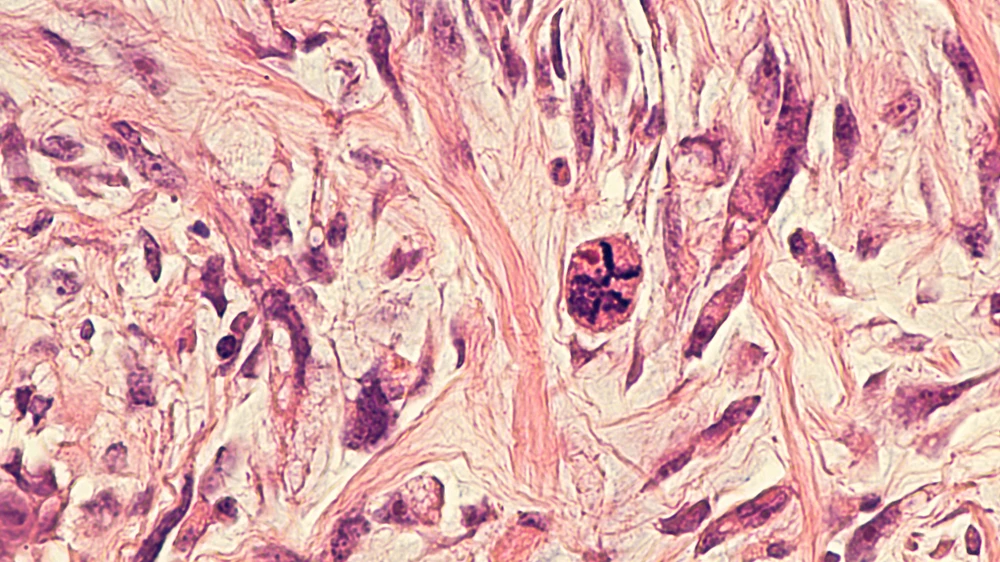

Phyllodes tumors, derived from the Greek word "phyllodes," meaning "leaf-like," are named for their characteristic leaf-like growth pattern under the microscope. These tumors can vary in size and grow rapidly, causing noticeable changes in the breast. They are distinct from more common types of breast cancers, such as ductal carcinoma, because of their origin in the stromal tissue rather than glandular structures.